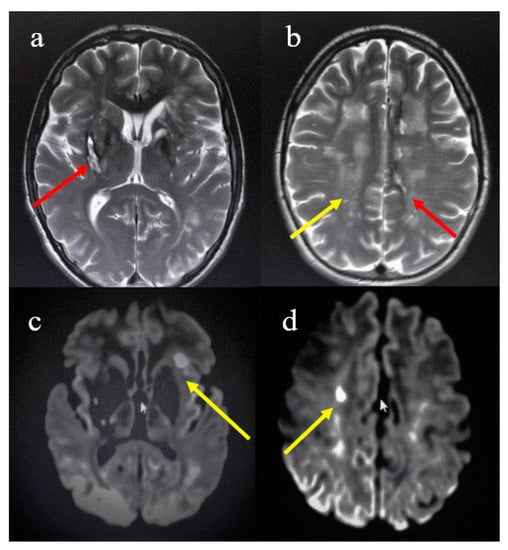

Case Presentation